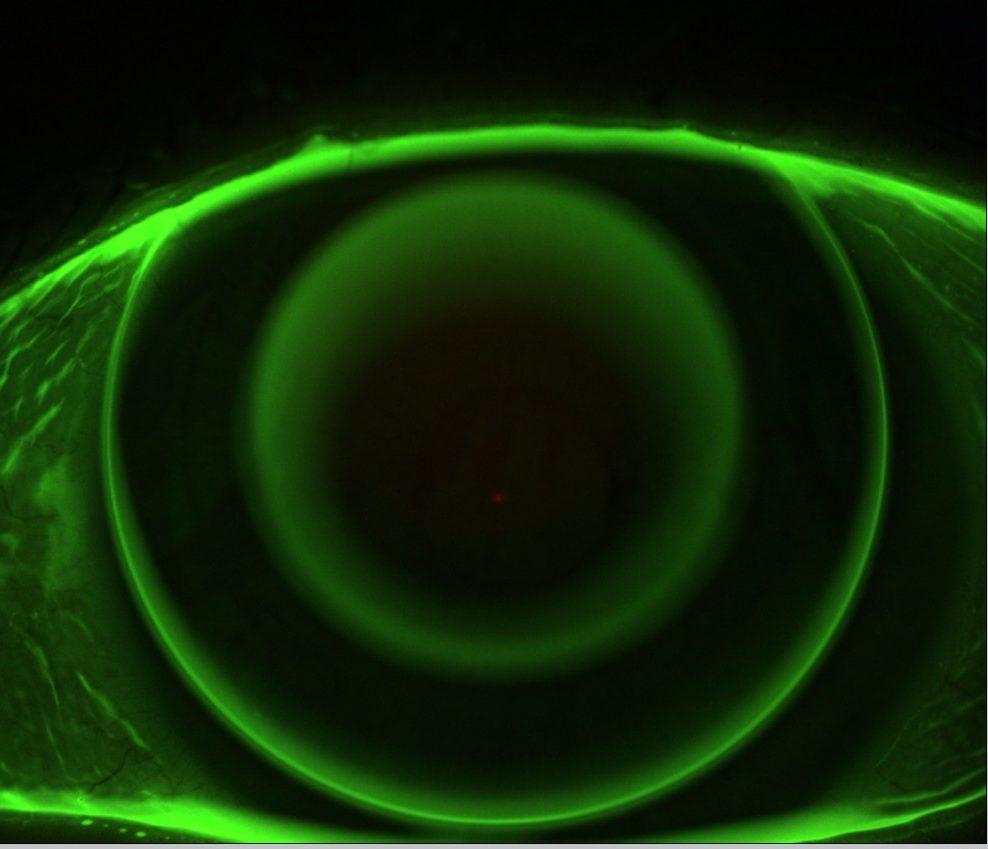

L’orthokératologie ou ortho-k est une technique qui a plus de 20 ans, non chirurgicale permettant de remodeler la courbure de la cornée durant la nuit à l’aide de lentilles de contact spécifiques. Ces lentilles sur mesure, vont modifier de manière contrôlée les rayons de courbure de votre cornée, et ce sans aucun appui sur cette dernière. Au réveil, vous retirez vos lentilles et votre vision reste nette jusqu’au soir !

Afin d’assurer la réussite de l’adaptation, nous évaluons vos besoins et effectuons une analyse détaillée de tous les critères de faisabilité. Pour définir la forme exacte de la cornée, nous mesurons à l’aide d’un topographe la géométrie de cette dernière en 3D, afin de déterminer les lentilles personnalisées à commander. Dès la première nuit, les résultats se feront sentir, et il faudra 4 à 7 jours environ, la myopie aura disparu.